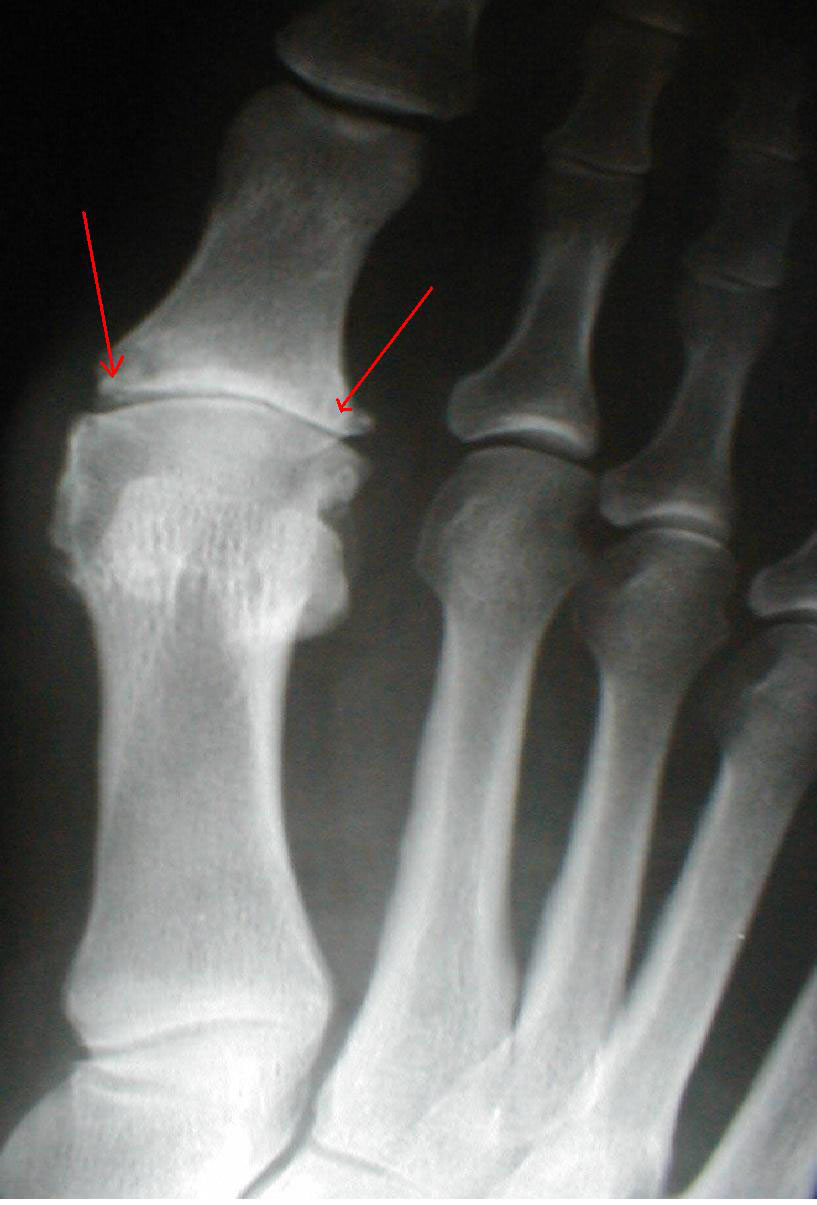

第五趾跖关节半脱位不排除第五趾骨近节基底部骨折?各位老师看看,对不